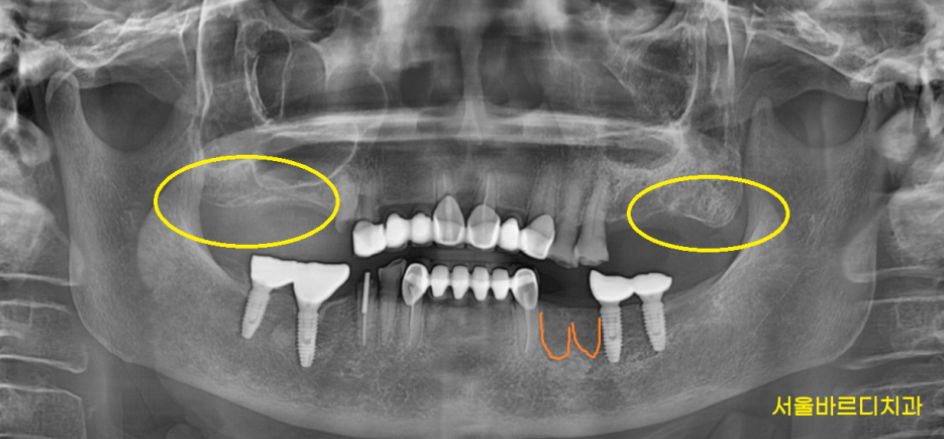

첫번째 잇몸뼈가 사라집니다.

치아가 빠졌는데 그대로 두게되면

잇몸뼈가 퇴화하게 됩니다.

얇디 얇은 종이처럼

뼈가 변하게 됩니다.

그래서 너무 늦게 오시게 되면

추석 효도선물로 임플란트를

해드리고 싶어도 못하는 경우도 생겨요ㅠㅠ

다수 치아가 상실되면

높이가 없어지면서

윗니 잇몸과 아래 잇몸이 닿게되는

놀라운 기적이 시작되는데 ㅠㅠ

턱 끝이 더 나와보이기도 하고요.